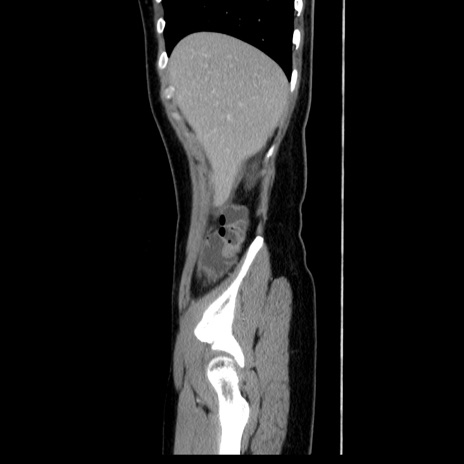

症例39(矢状断像)

【症例】40歳代女性

【主訴】上下腹部痛

【現病歴】2日目から下腹部痛あり。夜間は痛みで眠れなかった。昨日より上腹部痛と下痢が出現。臥位で痛みは軽快したため、休んでいた。本日になって臥位でも立位でも痛みが強くなってきたため救急要請。

【既往歴】子宮内膜症

【身体所見】部:平坦・軟、左上下腹部に圧痛あり、反跳痛あり。

【データ】WBC 21800、CRP 26.78

CT